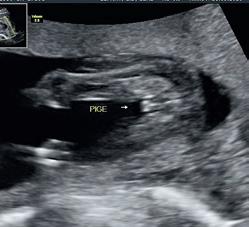

Cecilie: Vi fik en kønsscanning omkring uge 14-15, som viste, at vi ventede en lille pige – Ella. Efter scanningen fortalte Kathrine, at hun i forbindelse med igangværende certificering kunne tilbyde en misdannelsesscanning. Det ville vi gerne have, så vi tog imod en tid nogle uger senere. Jeg tog derind

alene, for vi havde så at sige scoret toppoint på alle scanningerne, så jeg tænkte bare, at det ville være hyggeligt med et ekstra kig derind. Da Kathrine scannede ansigtet, kunne hun ikke få den rigtige vinkel på munden. Så lavede hun et 3D-billede, som så lidt anderledes ud ved munden. Vi talte om, at det måske bare var navlestrengen, som lå i hovedregionen, der forkludrede billedet. Jeg fik tilbudt at komme igen næste dag, hvor Rikke Gaarn Kristensen foretog scanningen. Hun kunne se, at Ellas læbe ikke hang sammen. Der stod tiden lige stille.

Hvordan hjalp Kathrine og Rikke dig med at håndtere den situation?

Cecilie: Det var en voldsom ting at opdage, men det skete så fint og roligt. Kathrine tog mig i hånden, og vi fik alle tre en rolig snak om, hvad det kan indebære, og hvad næste skridt er. Det er kun hospitalet, som må stille den endelige diagnose, så de ringede til Aarhus Universitetshospital i Skejby og fortalte, hvad de havde opdaget. Rikke prøvede også at få fremrykket den tid, jeg havde på hospitalet ugen efter, så jeg ikke skulle vente så længe. Hun ringede også til Morten for at forklare det hele.